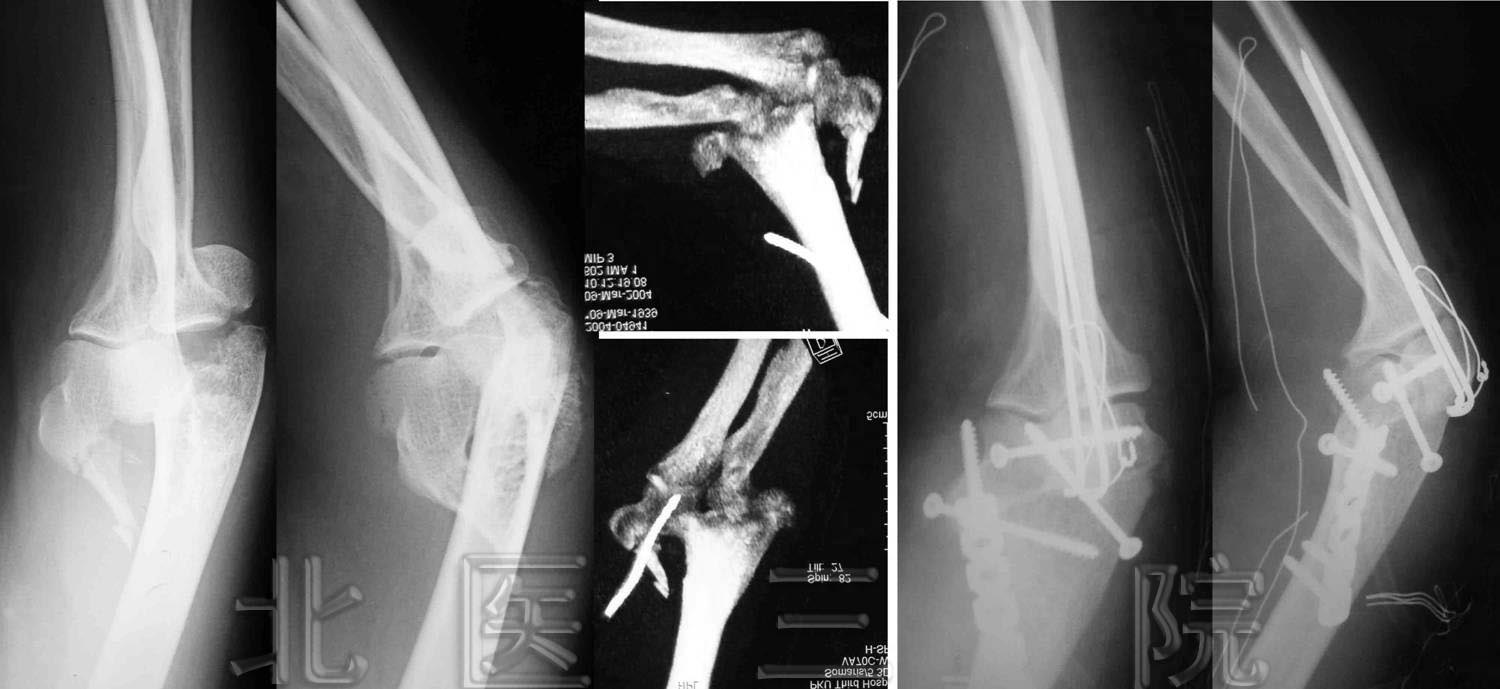

11年“断臂”终能伸屈

www.thebeijingnews.com · 2006-2-4 1:45:55 · 来源: 新京报

术前已出现严重骨缺损和骨萎缩,不日可恢复正常功能

本报讯(记者魏铭言通讯员姚永玲牛小燕)昨天,“断臂”11年的贾先生,在北医三

院骨科医生的指导下,终于可以重新自由伸屈自己的左臂了。

贾先生回忆,1994年10月,他在出差途中遭遇车祸,左胳膊开放性骨折,肱骨干完全

断开。医生为他实施了切开复位内固定手术。但时隔半年,他的左胳膊仍肿胀、疼痛得不

能活动。到医院检查发现,伤臂的桡神经损伤严重。此后,他接受了桡神经松解术等多次

手术,不但没有痊愈,左臂还出现了肢体内翻畸形。此后,经过多次手术仍不能治愈,医

生只能暂时拆除伤臂的外固定架,让左臂几乎成了“断臂”。

去年年末,贾先生拖着“断臂”来到北医三院骨科求治。医生检查发现,贾先生的伤

臂经多次手术,骨折处已出现严重的骨缺损和骨萎缩,必须重新植入新骨并牢固固定。院

方由4位医师共同为贾先生实施手术,首先彻底清除了“断臂”内的瘢痕及硬化骨质;然后,

对断臂处进行植骨;最后,精细的螺丝钉将新骨与旧骨密切、牢固地结合起来。

手术后两天,贾先生的左臂能抬起了。经过一个月的锻炼,终于可以自由伸屈。医生说,

再经过一段时间的功能训练,贾先生的左臂就可以拎东西,正常工作了。